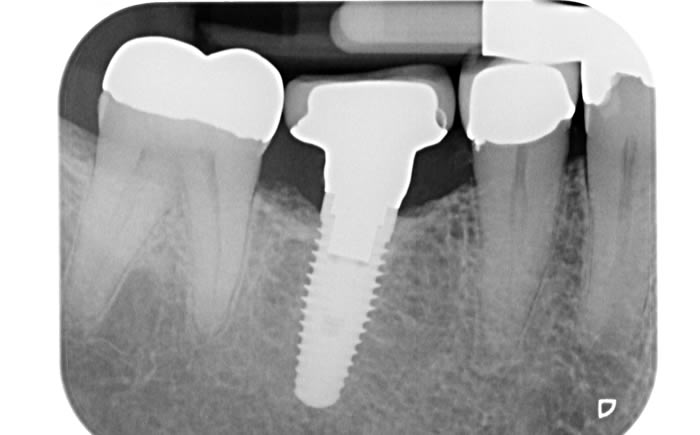

More back teeth replaced by dental implants

Case Three (2 images)

Case Four (4 images)

Case Five (4 images)

Case Six (8 images)

Case Seven (4 images)